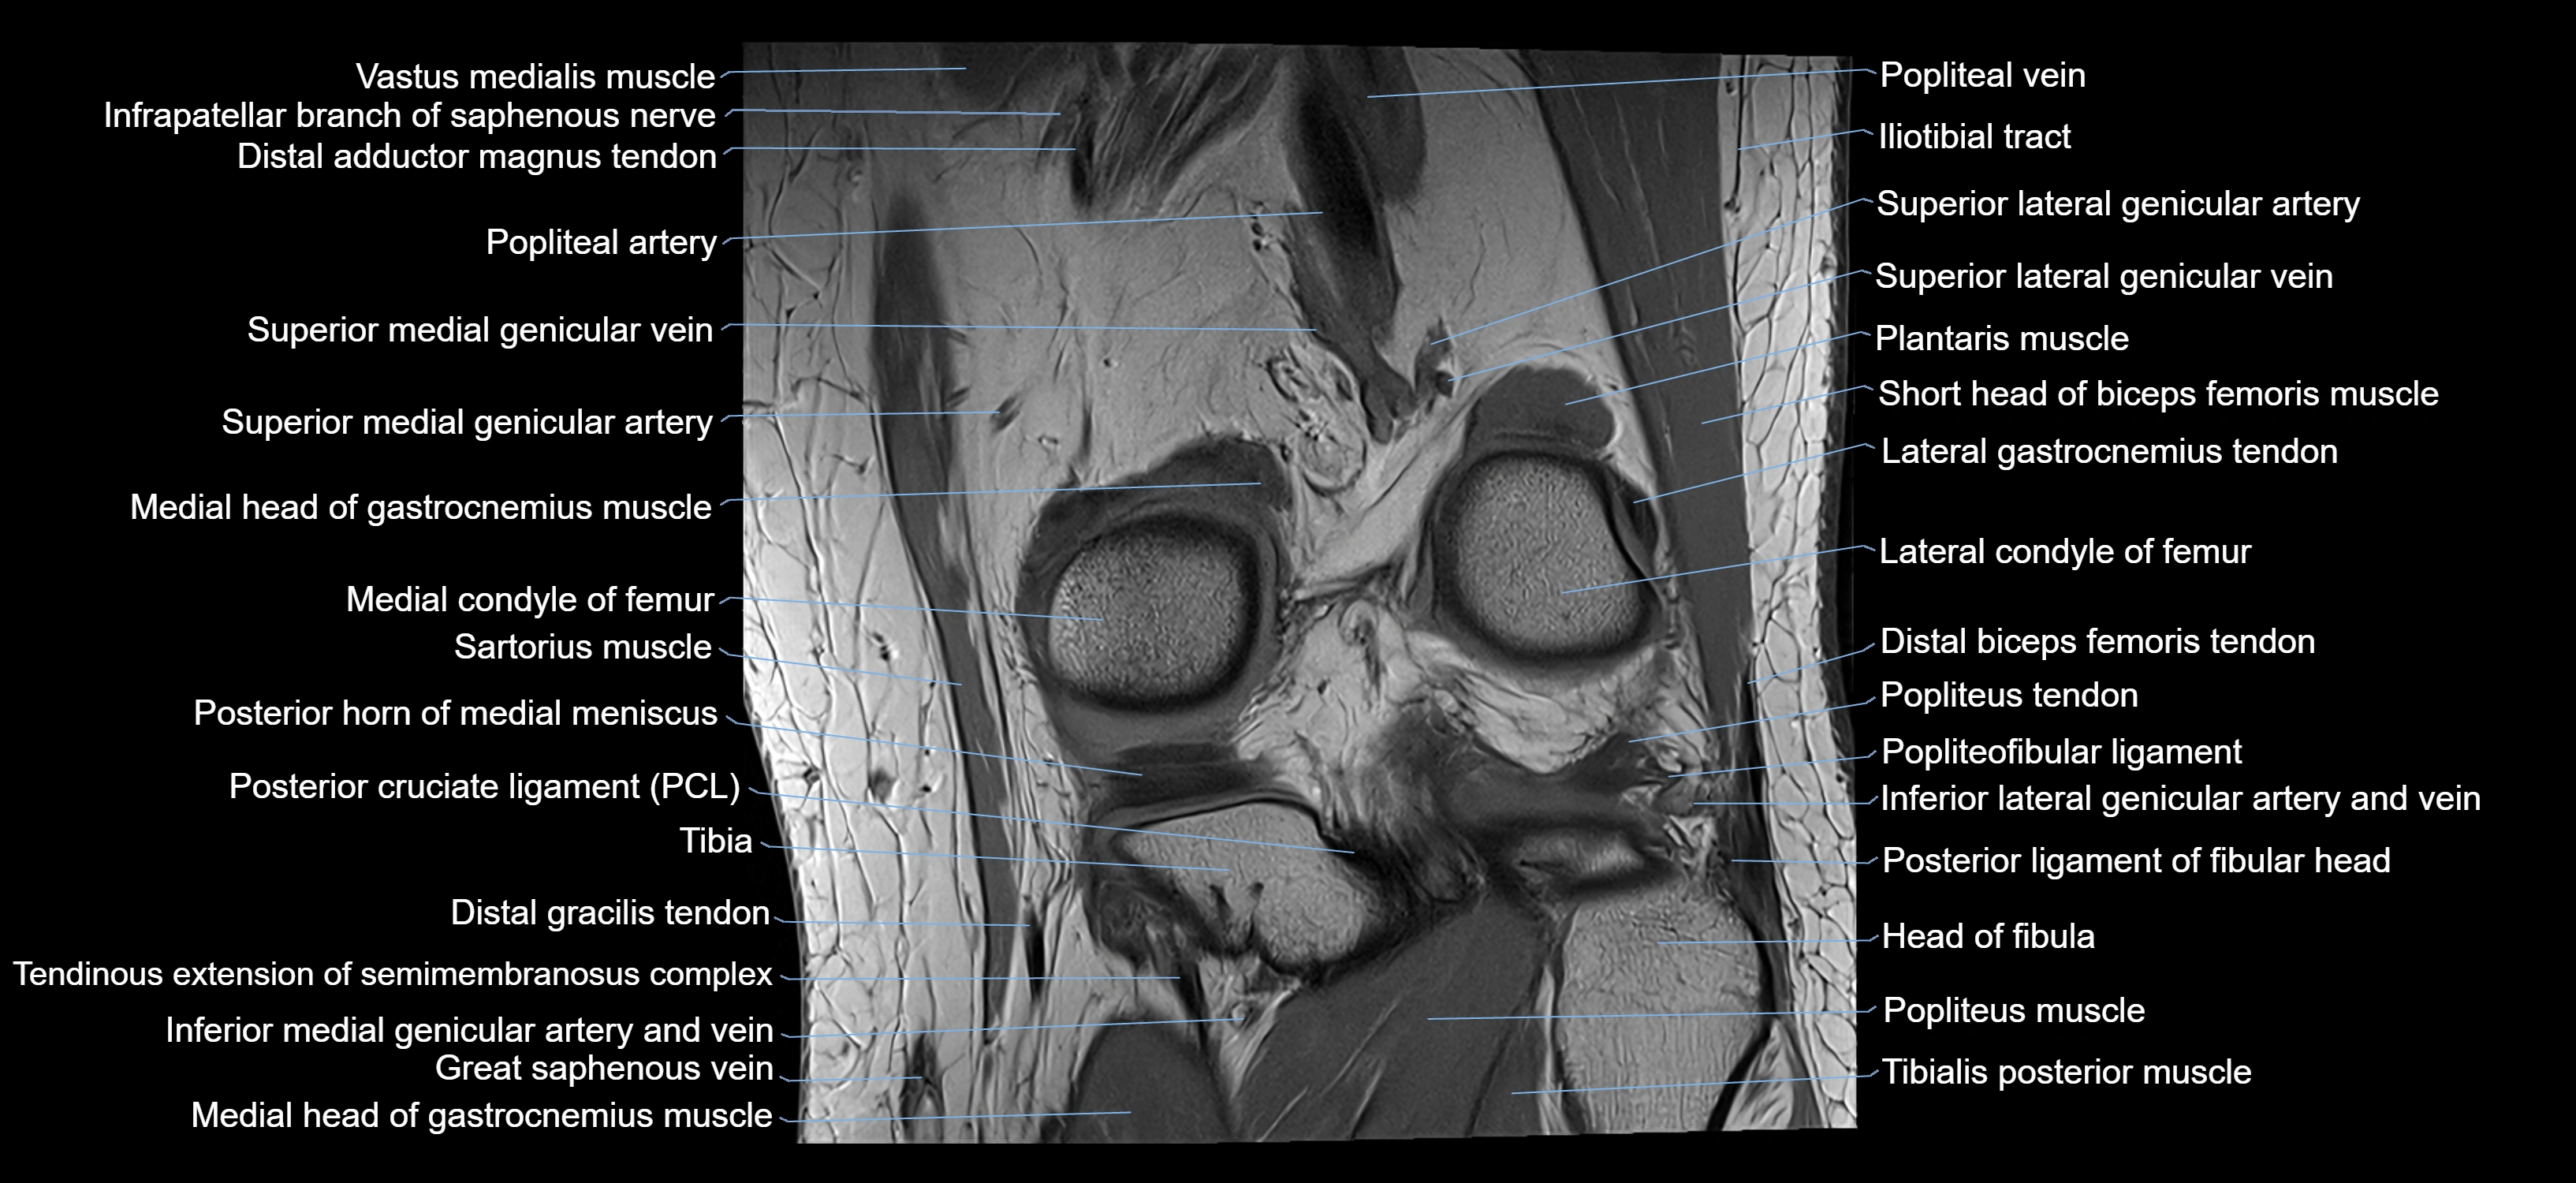

- Medial condyle of femur

- Medial head of gastrocnemius muscle

- Popliteal artery

- Popliteal vein

- Popliteus muscle

- Popliteus tendon

- Posterior cruciate ligament

- Posterior horn of medial meniscus

- Posterior ligament of fibular head

- Sartorius muscle

- Semimembranosus muscle

- Superior lateral genicular artery

- Superior lateral genicular vein

- Superior medial genicular artery

- Superior medial genicular vein

- Tibia

- Tibial nerve